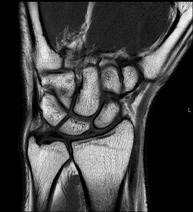

Exploració per a l'estudi de lesions en els tendons, els músculs i les articulacions. Molt útil per a la valoració de petites fractures inadvertides, lesions de lligaments i processos inflamatoris i degeneratius (artritis i artrosi). La durada aproximada és de 20 minuts. No utilitza radiació ionitzant. - RM de Mà / dits

Exploració per a l'estudi de les lesions en petites estructures anatòmiques de l'articulació que solen lesionar-se en pacients que pateixen luxació o inestabilitat crònica. L'estudi ve precedit per una injecció de contrast a l'interior de l'articulació, realitzada sota control de raigs X. La durada total dels dos procediments és de 50 minuts. - Artro-RM de Canell

Exploració per a l'estudi de les lesions en petites estructures anatòmiques de les seves articulacions com ara lligaments i cartílag. L'estudi ve precedit per una injecció de contrast a l'interior d'una de les articulacions, realitzada sota control de raigs X. La durada total dels dos procediments és de 50 minuts. - Artro-RM de Maluc